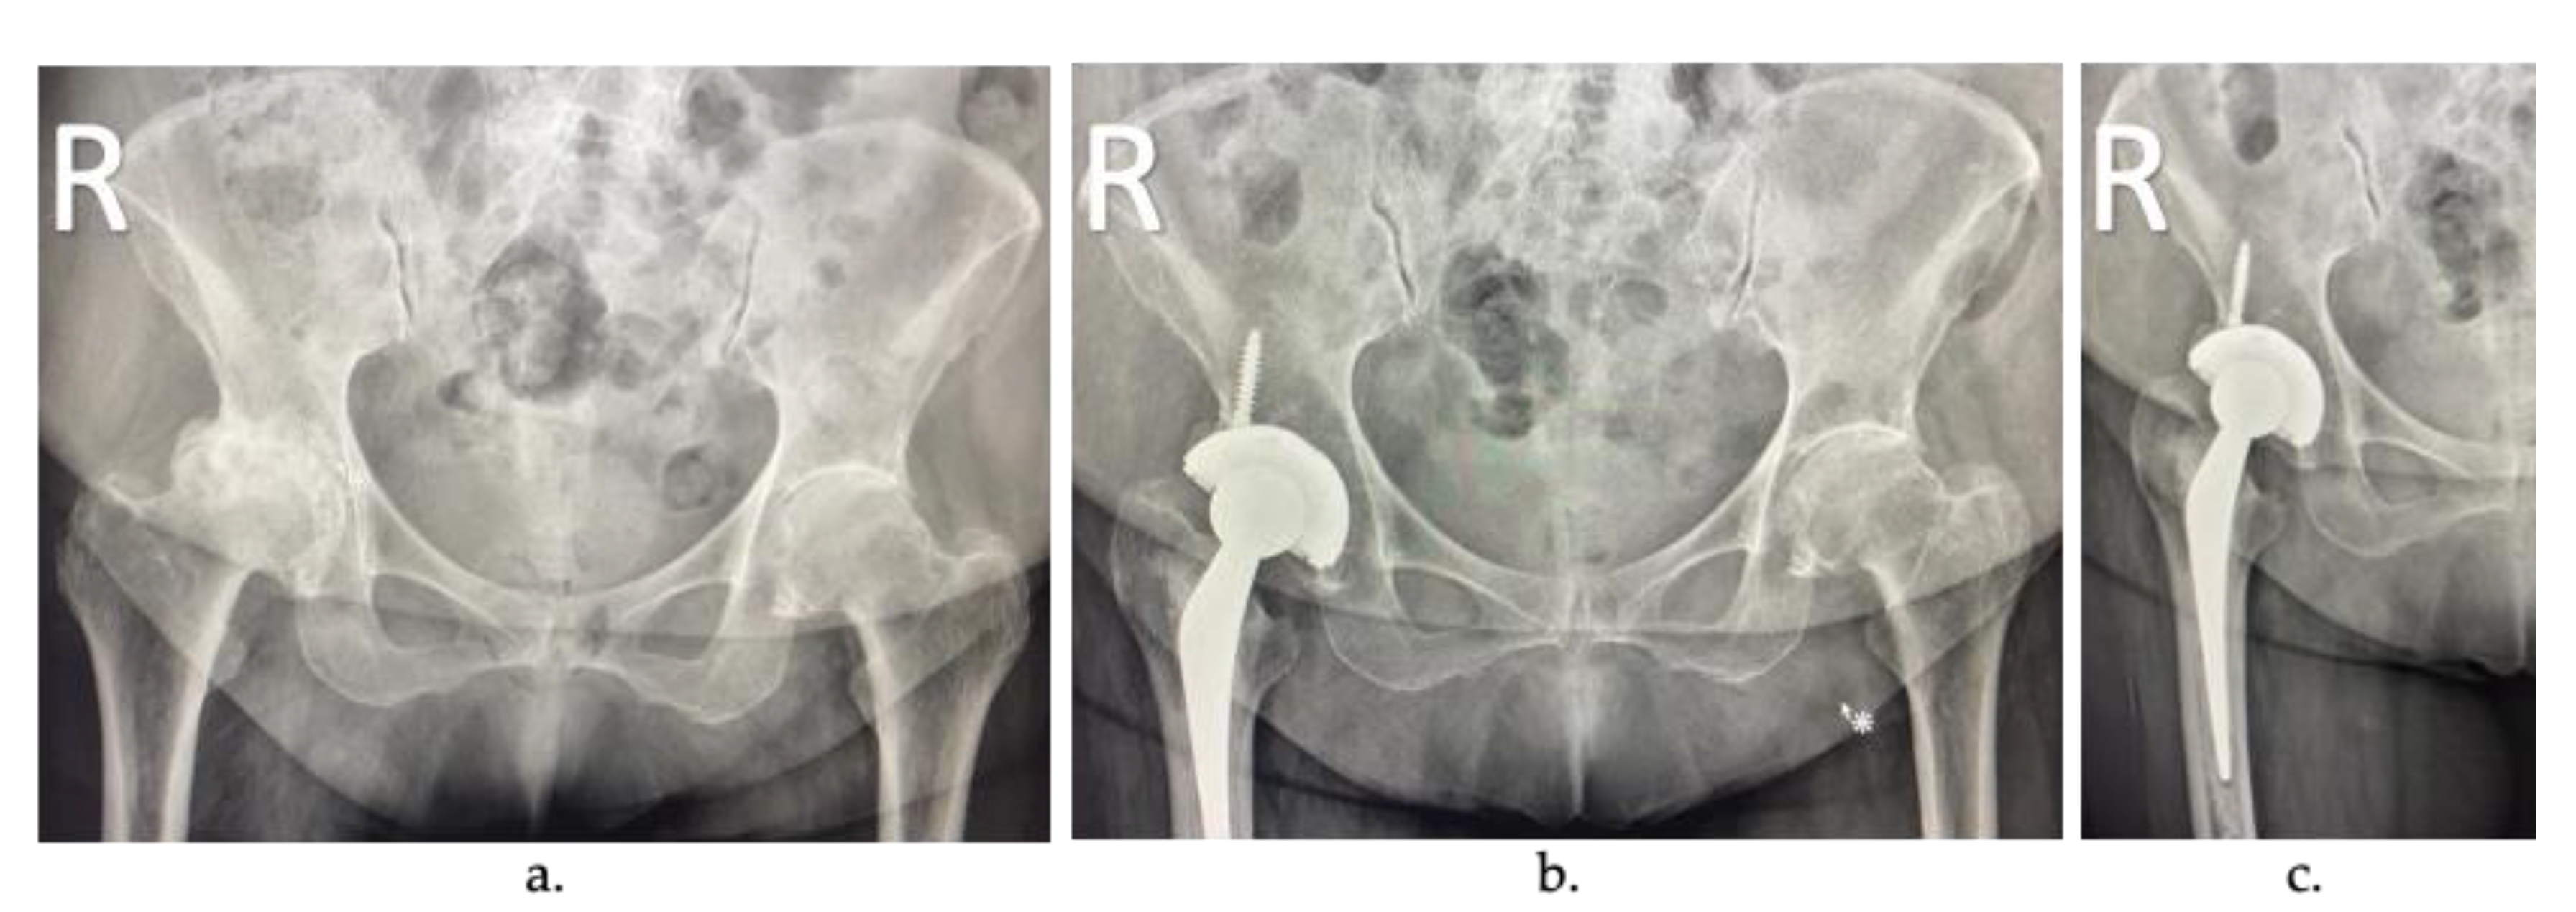

2. Arthroplasty